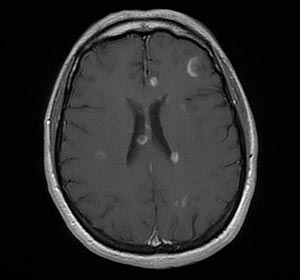

Информация о диссеминированном рассеянном энцефаломиелите